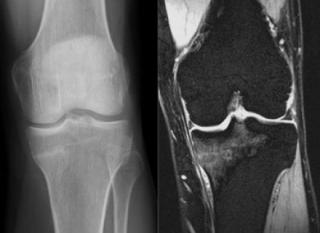

МРТ или КТ коленного сустава

МРТ или КТ коленного сустава - это два высокоэффективных метода диагностики организма человека, а вот какой из них и в чем лучше, давайте попробуем разобраться. В зону колена входят ткани разного характера: костные ткани - бедренная кость, малая и большая берцовая кость, хрящи суставной поверхности, мениски; мягкие ткани - связки, мышцы сухожилия, сосудисто-нервные пучки, жировое тело. Из-за физики получения изображения кость лучше всего визуализируется на

МРТ – ведущий метод диагностики при травматических повреждениях суставов

При травмах различных суставов важно получить наиболее точную информацию о целостности связок, менисков, наличии отека и воспаления. Лучше всего с поставленной задачей справляется магнитно-резонансная томография. МРТ выполняется для оценки повреждений, полученных в результате спортивных травм и в быту. МРТ также проводится для диагностики в тех случаях, когда у пациента не было травмы, но присутствует болевой синдром.

Главная задача для МРТ – выявление повреждения связок и оценка мягкотканных структур. Диагностика артроза при выполнении МРТ также возможна. Томография позволяет выявить отек мягких тканей и определить его выраженность. Также МРТ видит изменения в тканях вокруг суставов.

Для диагностики травматических изменений применяются и другие исследования. Компьютерная томография и рентгеновское исследование превосходят МРТ в возможности выявления переломов костей, но существенно уступают в возможности оценки мышц, связок, менисков, отека и воспаления. По этой причине при острых травмах иногда возникает необходимость, выполнения как КТ для оценки целостности костей, так и МРТ для диагностики повреждений мягкотканных структур.